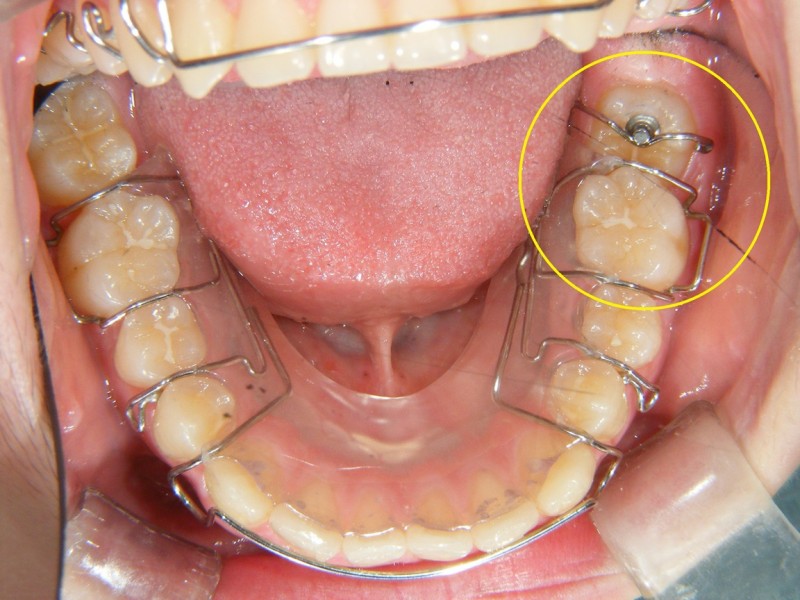

↑歯型を採って、このような装置を作りました。

バネの力で、奥歯を起こします。

↑装置をセットしたところです。

1日、14時間以上装着します。

月に1回、装置を調整します。